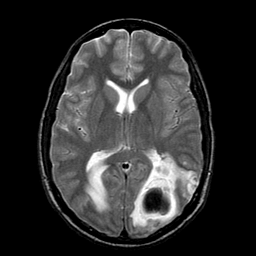

Sarcoma, MR Study #1 mr-t2 -- Slice #12

[Home][Help][Clinical] Slice 12